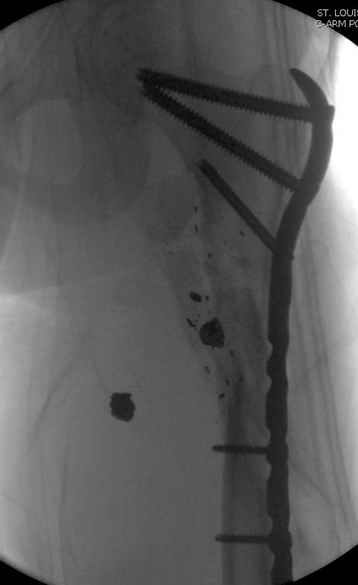

Молодой, с общим состоянием без проблем. Больной соперирован в день поступления и через два дня после операции выписан, так что не успел развиться гной.

Перелом низкоскоростным оружием, типа пистолетного, так что не стали гоняться за пулевыми фрагментами. С нервом пока подождем, иногда нерв восстанавливается если не прямое попадание в нерв, а "сотрясение" (shock wave injury).

Из всех типов фиксации взяли малоинвазивную технику мостовидной пластиной, использовали Locking проксимальную Synthes пластину.